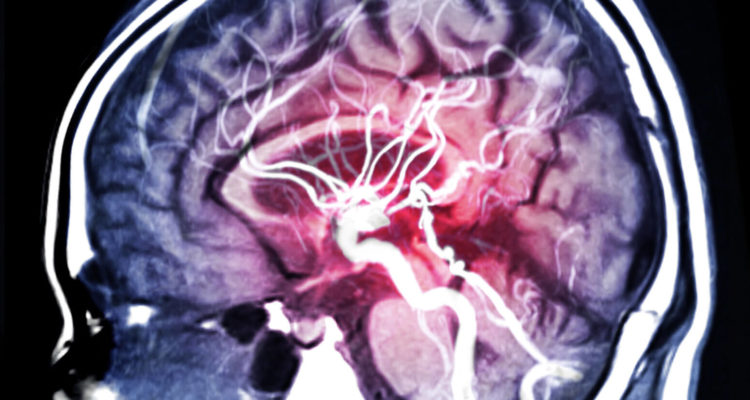

Дослідники проаналізували дані більш ніж 210 тис. учасників довгострокових медичних спостережень. З них у 15,8 тис. спостерігалися серцево-судинні захворювання, у тому числі майже 9,8 тис. випадків ішемічної хвороби і майже 6,2 тис. випадків інсульту. Виявилося, що більш високий запальний потенціал в дієті був пов’язаний з підвищеним ризиком серцевих захворювань, ішемічної хвороби серця та інсульту. Ці співвідношення були постійними для різних груп і статей і залишалися значними після подальших Коригувань для інших показників якості харчування.